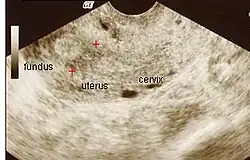

La historia del acontecimiento del embarazo seguido por la dilatación y el legrado liderizado por la amenorrea secundaria o a la hipomenorrea es común. La histeroscopia es el estándar de oro para el diagnóstico. 3 La proyección de sonohisterografía o histerosalpingografía podría revelar el grado de la formación de la cicatriz. El ultrasonido no es un método confiable de diagnosticar el Síndrome de Asherman. Los estudios de la hormona muestran los niveles normales constantes con la función reproductiva.